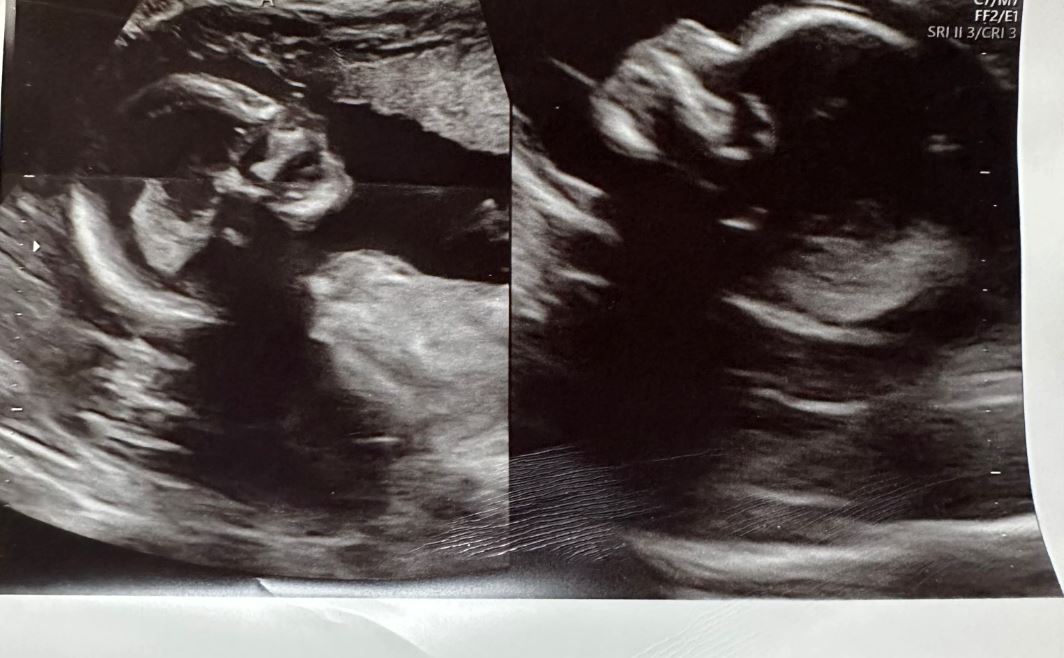

Menurutnya, ketika menjalai rutin ultrasound selama lapan minggu pada Mei lalu, juruterapi urut dan ibu kepada tiga anak itu baru mengetahui yang dia bukan sahaja hamil anak kembar, tetapi mempunyai janim dalam kedua-dua rahimnya.

Hasil pemeriksaan juga mendapati, kedua-dua anak dalam kandungannya di dua rahim membesar secara normal dan baik.